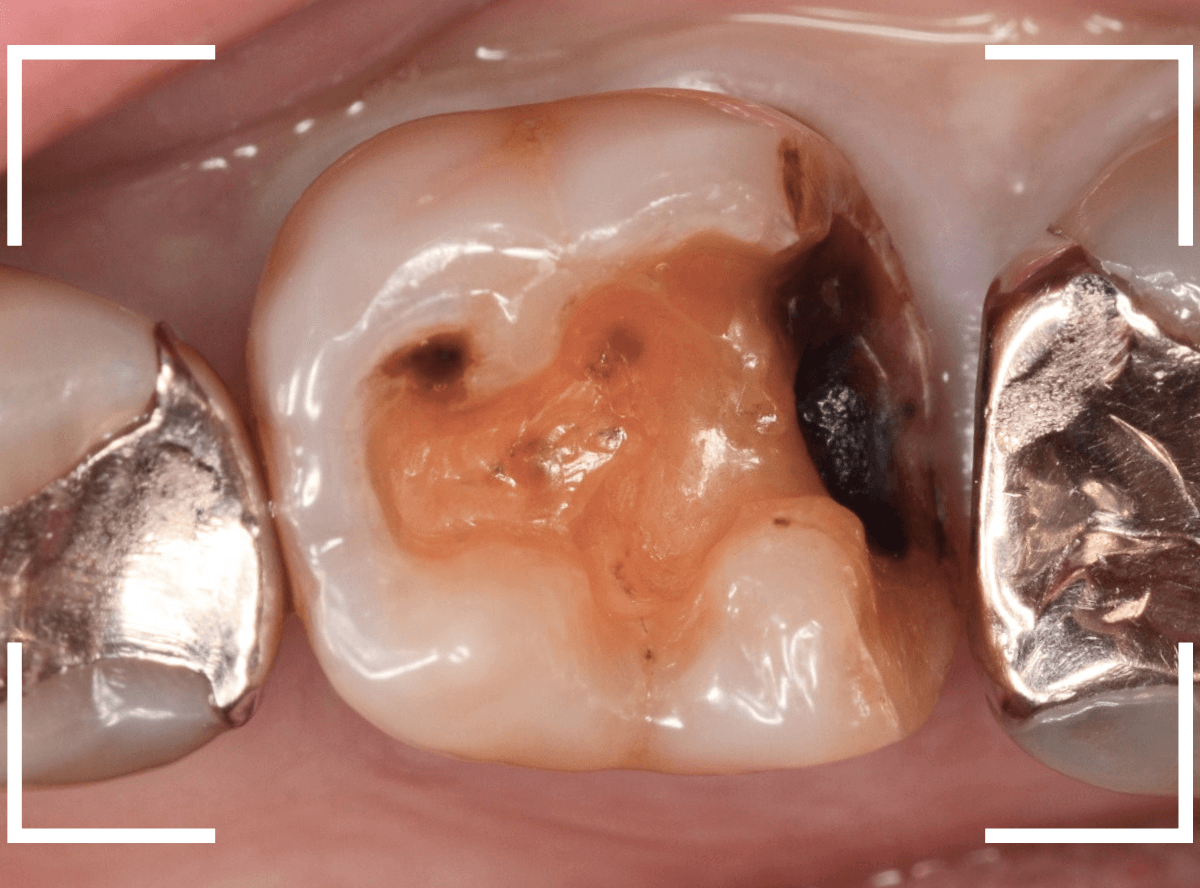

メンテナンス中に、虫歯が見つかった方のケースです。

虫歯の治療については、

「歯と歯の間の虫歯/case.26」

をご覧ください

https://kp-dental.com/blog-post/377348

大きな虫歯でしたので、しばらく経過観察しましたが、特に症状もありませんでしたので、患者さんの希望に伴い、ジルコニア・インレーで治療をします。